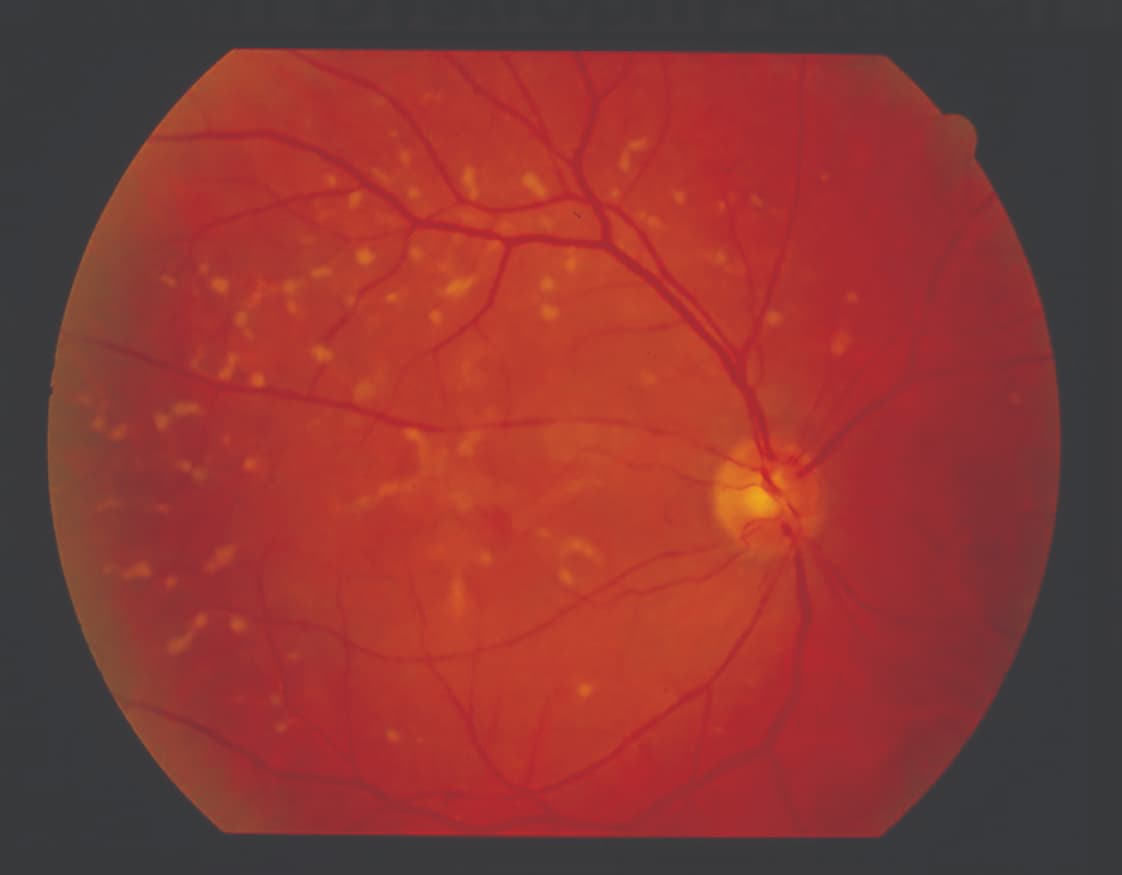

Figure 3: A color fundus photo of a patient with pattern dystrophy. Note the irregularly shaped drusen-like deposits.

Pattern dystrophy is a less common group of disorders that present with a variety of pigmentary changes affecting the macula. When these dystrophies progress to significant RPE atrophy, the resulting fundus picture may mimic GA. A family history and detailed imaging are valuable tools in making the correct diagnosis. Other IRDs are much less common; yet, once they are sought, they can be found. Some of these conditions exhibit a phenotype characterized by choroidal atrophy. They do not typically have drusen, but they can have large, circular lesions that resemble GA. Genetic testing should also be performed in these situations (Figure 3).